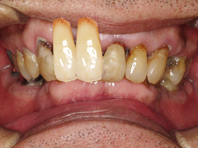

上顎にインプラント治療予定ですが、歯を支える骨も溶けて薄くなってしまっている状態でした。

この患者さんの歯茎はもうすでに腐り骨は溶けている状態だったので、骨を再生せずにインプラントを行なうと、写真のように歯茎の上の方からインプラントを入れることになり、非常に不自然な完成となってしまいます。